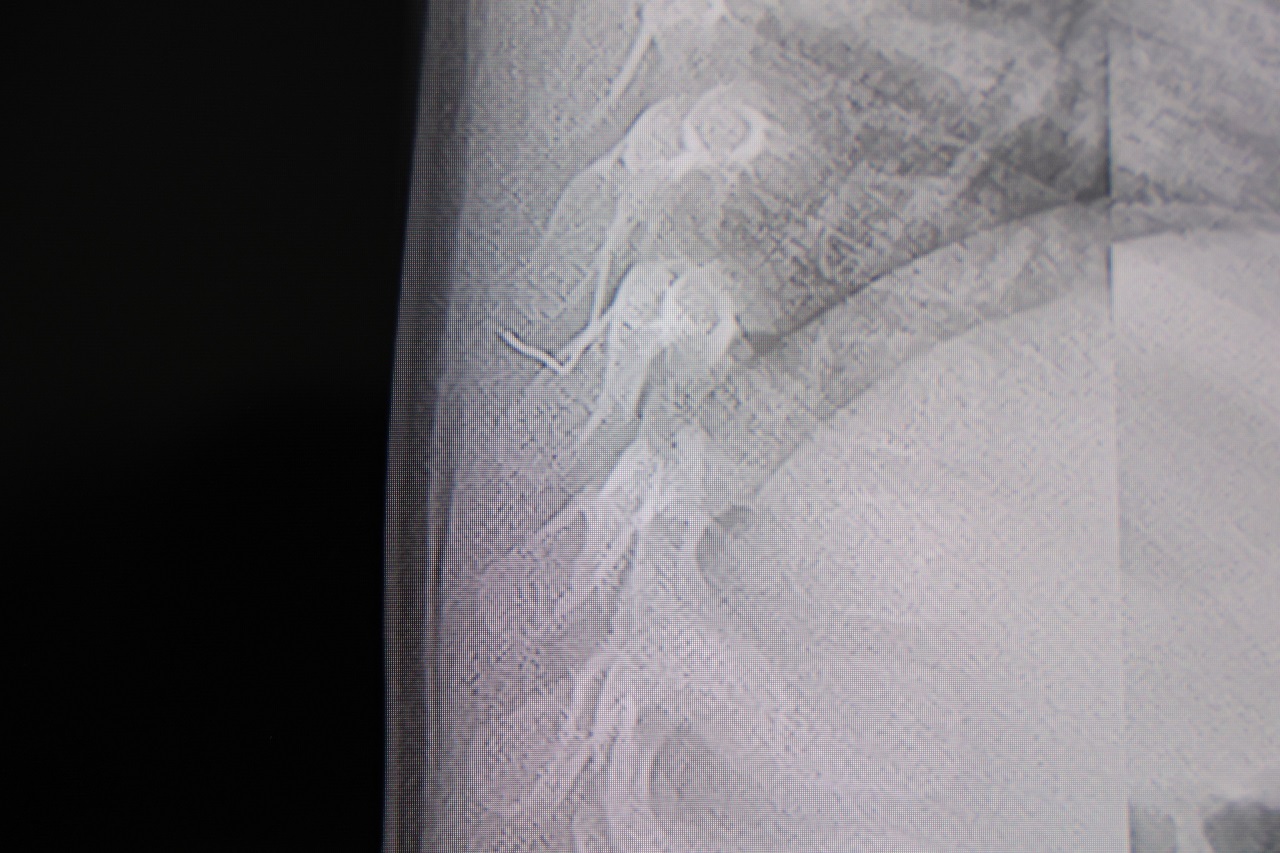

TEL, OMURİLİK KANALINA YAKIN VE AKCİĞER ZARINA DAYANIYORDU

Prof. Dr. Altun’un değerlendirmelerine göre, söz konusu metal tel; bebeğin omurilik kanalına çok yakın, akciğer zarına doğru ilerleyen bir noktadaydı. Bu bölgede gelişebilecek enfeksiyonun hayati risk taşıyabileceği, hatta ilerleyen yaşlarda ciddi omurilik hasarlarına neden olabileceği bildirildi.

“Hastayı tamamen uyutmadan, lokal anestezi ve sedasyon altında müdahale ettik. Cilt altından çıkarılan yabancı cisim yaklaşık 2 santimetre uzunluğunda, zımba teline benzer bir metal parçaydı. Bu tel alınmasaydı, enfeksiyon, omurilik hasarı, akciğere batma ve hatta tümör benzeri reaksiyonlara yol açabilirdi” dedi.